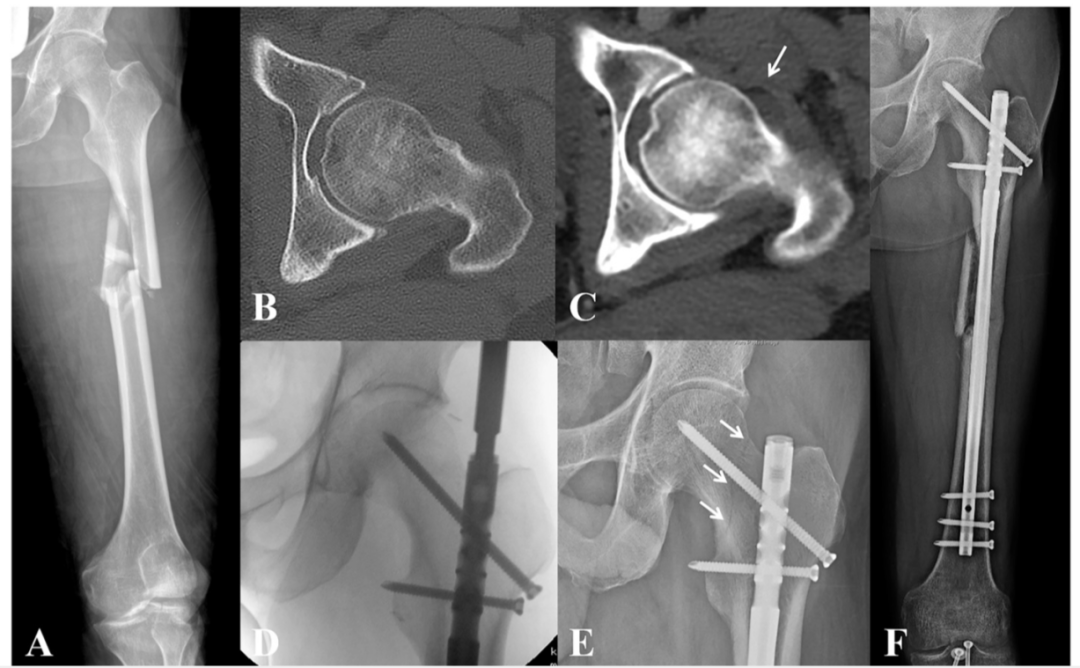

图1 CT软组织窗可见由关节积脂血症导致的囊性征(箭头所示)。测量图B黄色圈内CT值平均为-17。

图2 所有纳入病例的研究方法。

图3 一例高能量股骨干骨折(A)。图B可见在CT骨窗上,未见骨折线,在软组织窗(C)上,可见由关节积脂血症导致的囊性征。因此予以固定股骨颈。在术后6周复查(E),可见明显骨折线。